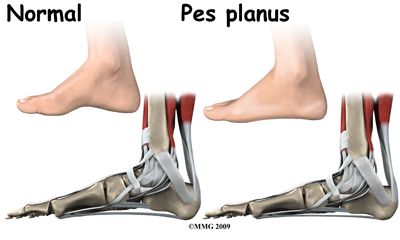

Flatfeet (also known as pes planus) describes a condition in which the longitudinal (lengthwise) and/or medial (crosswise) arches of the foot are dropped down or flat. The entire bottom of the bare foot is in contact with the floor or ground surface during standing, walking, and other weight bearing activities. Congenital means that the condition is present at birth in one or both feet. When only one foot is affected, the problem is referred to as unilateral pes planus or flatfoot. When both feet are involved, the condition is bilateral flatfeet. Sometimes the term ‘fallen arch’ is used, but doctors prefer not to use this term in favor of the more accurate medical term ‘pes planus.’

Even if the deformity does not fully correct with age, it does not always cause direct problems with the foot, although the altered biomechanics due to the flatfoot can still affect the alignment of the lower extremity chain. The shin, knee, hip and back are all affected by the position of the foot, so if pain in any of these areas crops up later in life, the flat foot will be noted as a contributing factor and will need to be addressed at that point. It should be noted that flatfeet can be an inherited condition so looking at the feet of the parents may give an indication as to whether or not the flatfeet will correct as the child ages.

Flexible flatfoot refers to a foot that looks flat when standing but appears to have an arch when the foot isn't resting on the floor or against a flat surface. In the flexible flatfoot, the bone alignment is usually normal but the supporting ligaments are lax or loose which creates joints that are hypermobile (move too much). As the soft tissues and joints of the foot and ankle try to maintain a normal foot position, increased stress is placed on them. This can lead to fatigue and loss of strength resulting in a sagging of the arch. This then affects the chain of anatomical structures all the way up the leg.

For most young children, the flexible flatfoot deformity is mild and causes no symptoms. They do not suffer from pain, swelling, or sore feet. Children with flexible flatfoot deformity may wear out shoes a bit differently from a normal person, but this is not usually any reason to be concerned.